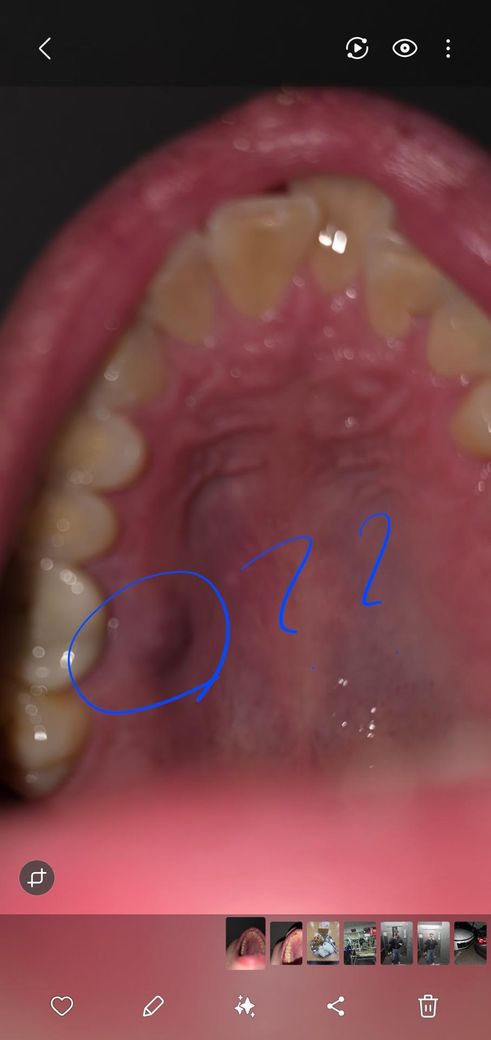

입천장쪽에 물집(?)인지 돌기인지 났는데 이게 뭘까요

한 일주일정도 된것같고 통증은 없어요, 혀로 만져봤을때는 물집 비슷한 느낌이에요.

뭔지좀 알려주시면 감사드리겠습니다.ㅠㅠ

• 주어진 정보를 토대로 정확하게 감별 및 진단 내리고 무어라 이야기 하기는 제한적이고 조심스럽습니다만, 점액낭종 소견이 아닐까 싶어 보입니다. 양성 병변이며 경과관찰 후 심해지거나 지속되어 사라지지 않는다면 이비인후과 진료 및 치료를 받아보는 것이 어떨까 싶어 보입니다. 그렇지만 우려스럽고 걱정되어 빠른 진단 및 치료를 희망한다면 바로 병원에 가보시는 것도 괜찮은 방법이 될 수도 있겠습니다.